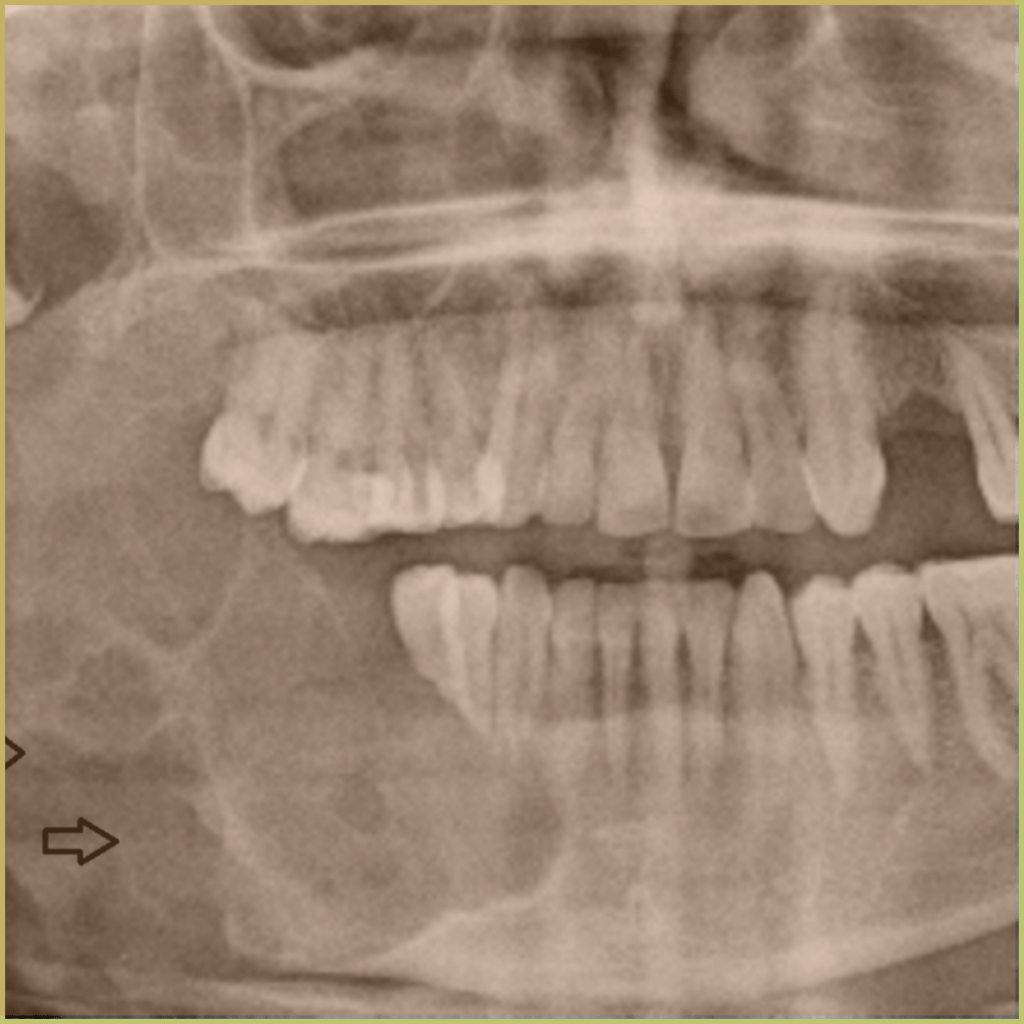

AMELOBLASTOMA

Ameloblastoma is a rare benign but aggressive odontogenic tumor derived from the epithelium of odontogenic ectodermal origin. The cause of ameloblastoma is not well understood. Rarely they develop into a malignancy (malignant ameloblastoma or ameloblastic carcinoma). The unicystic variant of ameloblastoma is less aggressive and is managed more conservatively. The common clinical presentation includes:

- Unilocular or multilocular osteolytic radiolucency with sclerotic borders.

- Often presents in association with unerupted third molars.

- Root resorption, tooth displacement and jaw expansion possible.

- Cortical perforation may occur.

- More common in the lower jaw (80%) than in the upper jaw.

- Typically slow growing but aggressive.